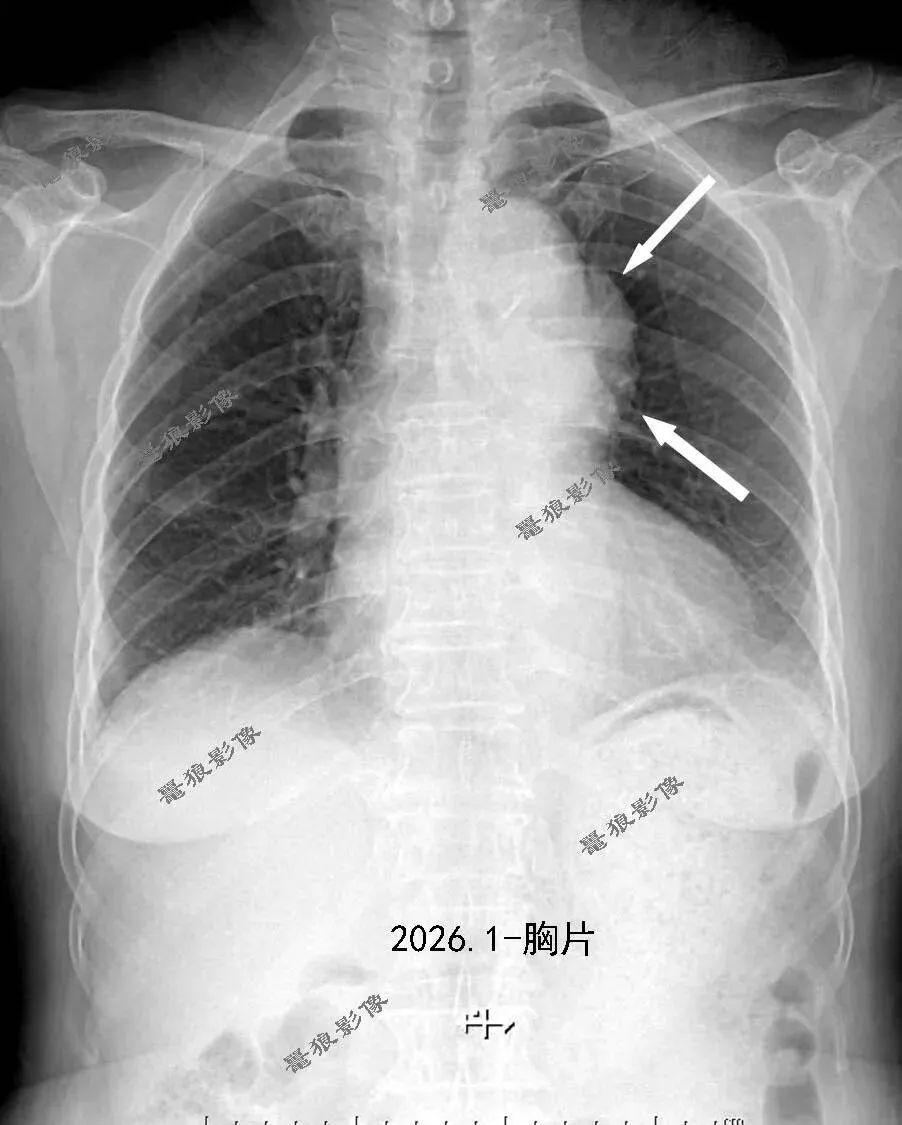

一、入院常规胸片提示:

与前片2022年4月对比,新增主动脉弓旁瘤样软组织密度影,考虑主动脉瘤可能性大,请密切结合临床,建议进一步检查。